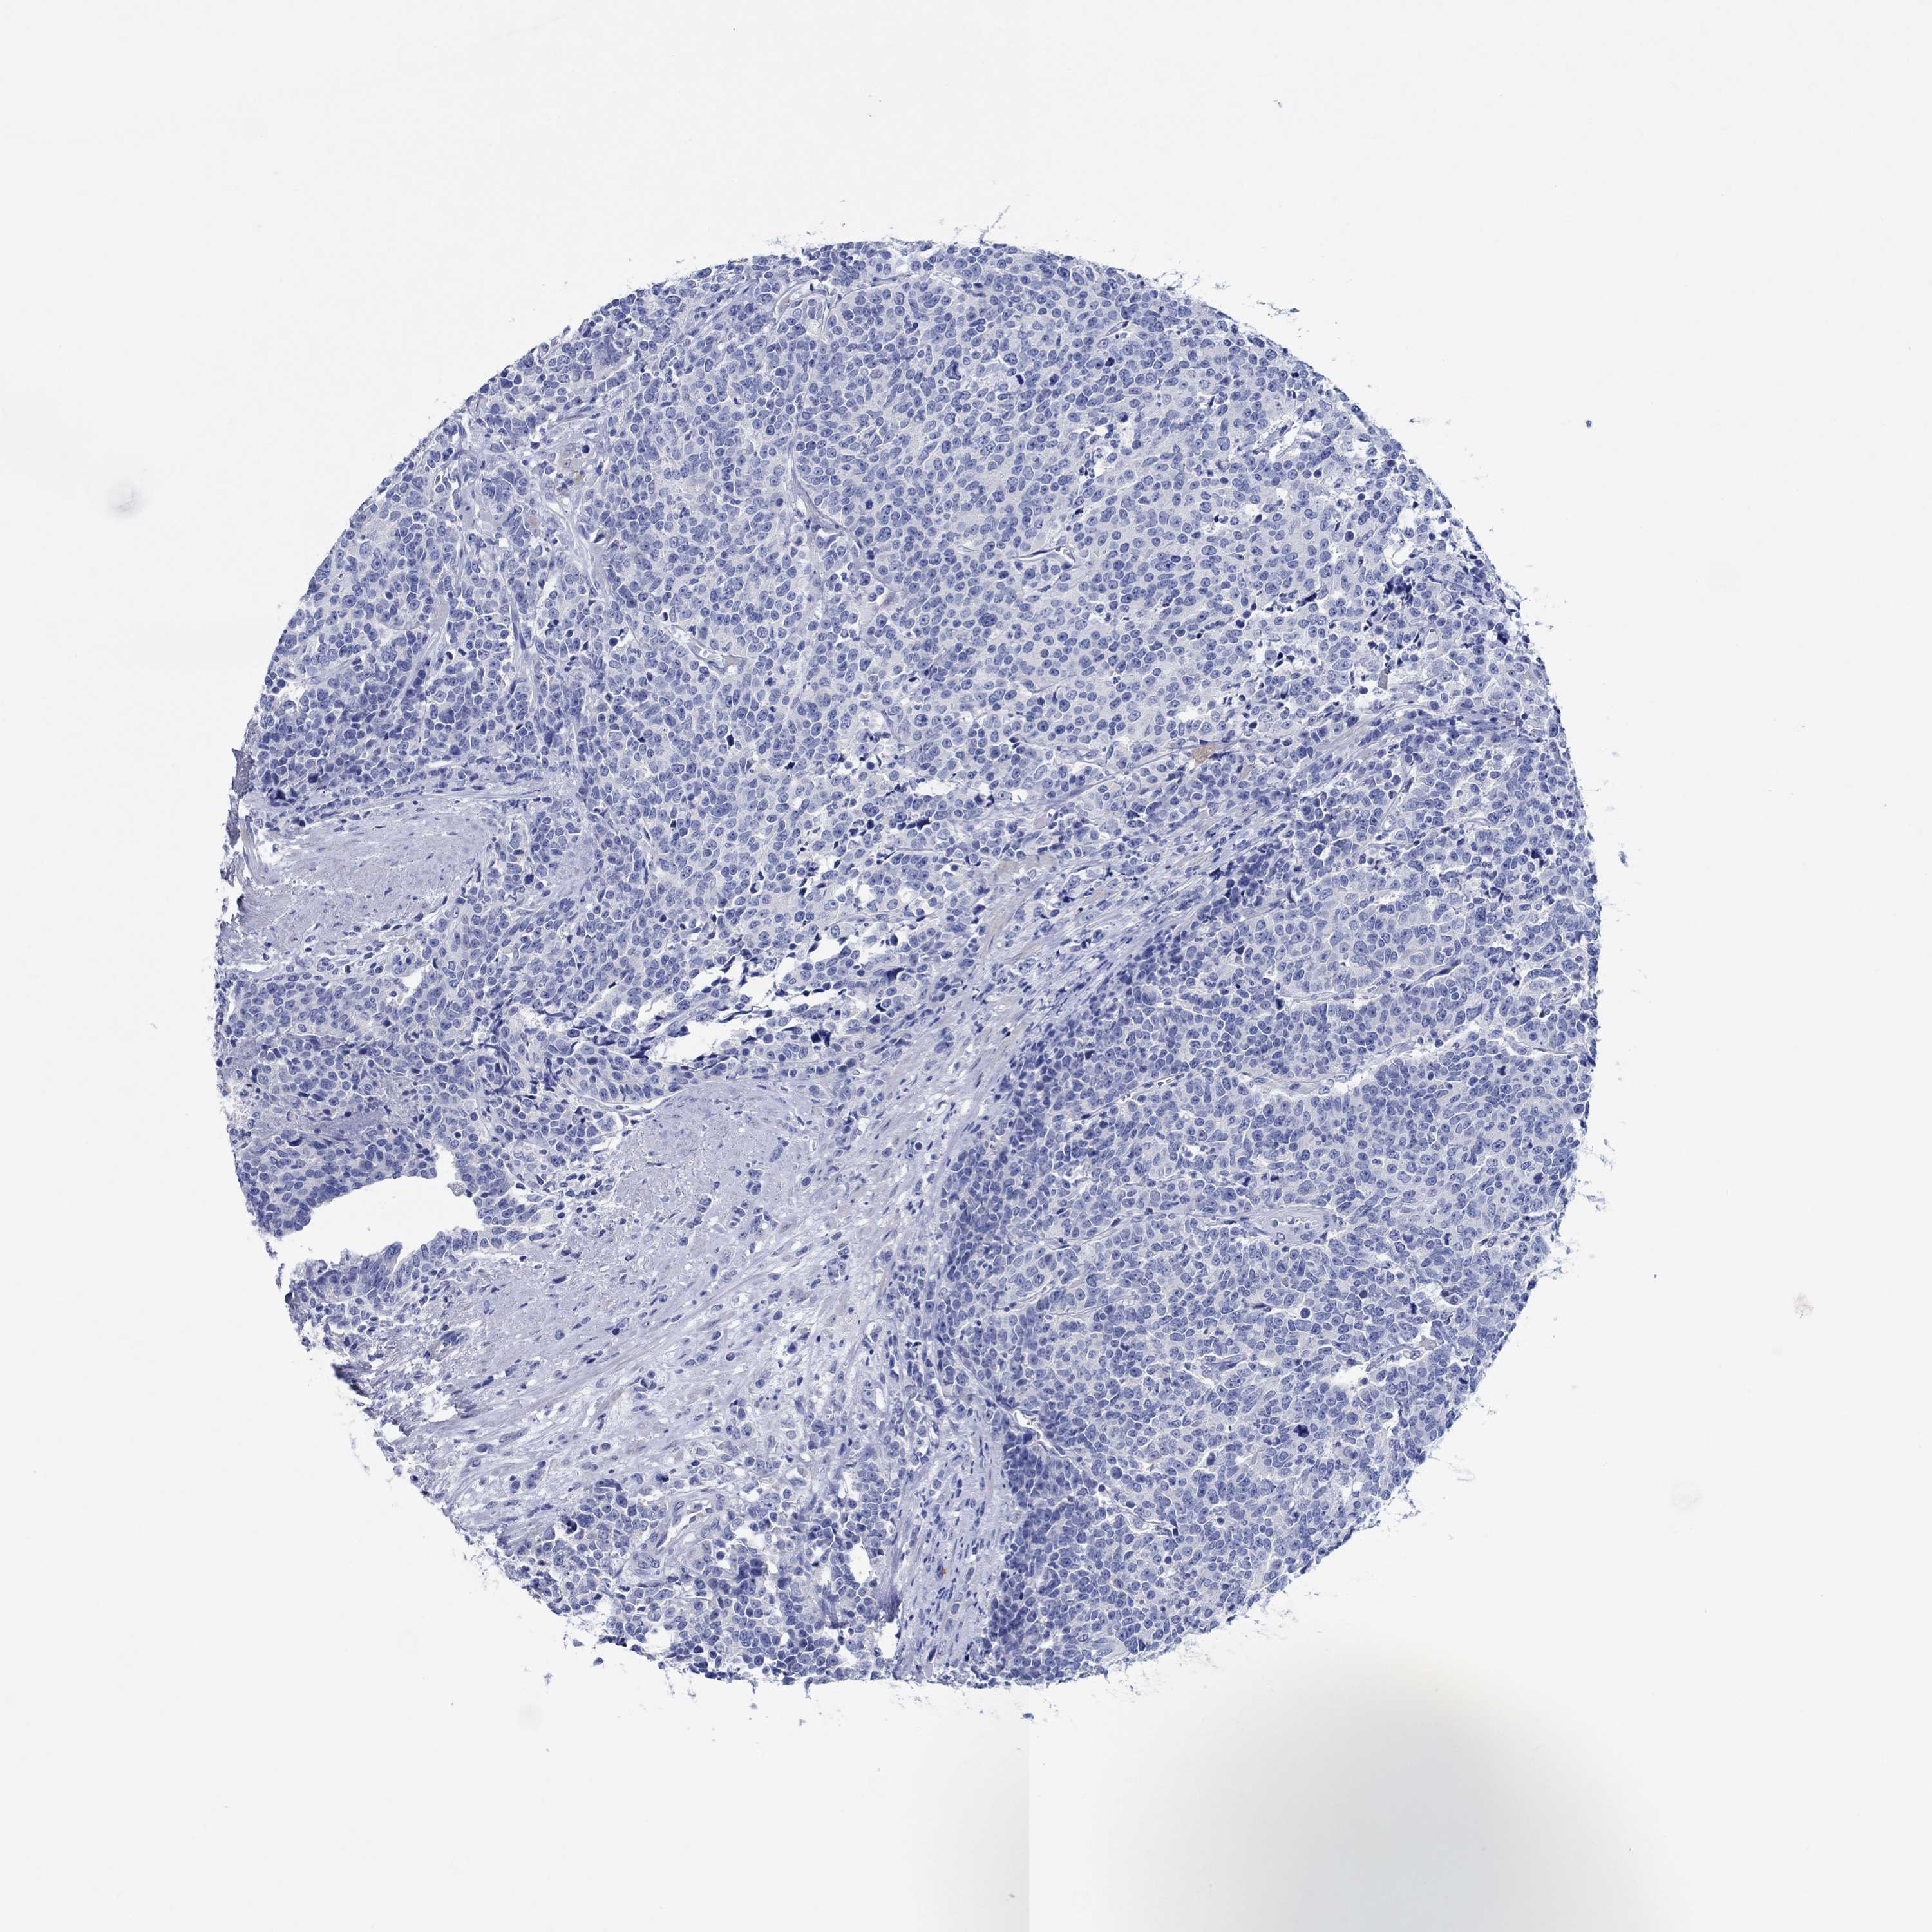

PROSTATE CANCER - Protein expressioni

A mouse-over function shows sample information and annotation data. Click on an image to view it in a full screen mode. Samples can be filtered based on level of antibody staining by selecting one or several of the following categories: high, medium, low and not detected. The assay and annotation is described here.

Antibody stainingi

Antibody staining in the annotated cell types in the current human tissue is reported as not detected, low, medium, or high, based on conventional immunohistochemistry profiling in selected tissues. This score is based on the combination of the staining intensity and fraction of stained cells.

Each image is clickable and will lead to virtual microscopy that enables deeper exploration of all samples and also displays staining intensity scores, fraction scores and subcellular localization as well as patient and tissue information for each sample.

Antibody HPA031636

Antibody HPA076665

Staining

High

Medium

Low

Not detected

Intensity

Strong

Moderate

Weak

Negative

Quantity

>75%

75%-25%

<25%

None

Location

Nuclear

Cytoplasmic/membranous

Cytoplasmic/membranous,nuclear

Adenocarcinoma, Low grade

Adenocarcinoma, NOS

Adenocarcinoma, Medium grade

Adenocarcinoma, High grade